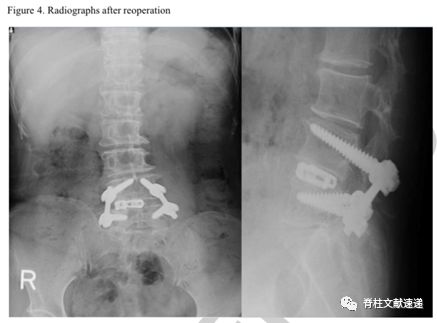

术前资料